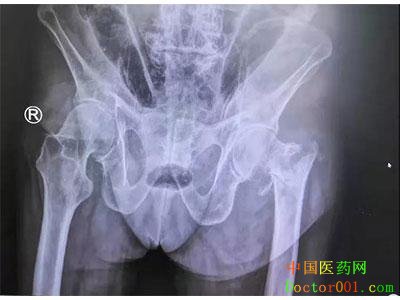

近日,我院骨一科成功为一名九旬高龄老人实施了“股骨闭合复位髓内针内固定术”,术后老人恢复良好,患者及家属表示满意。 《案例》详情: 陈爷爷今年99岁,2019年8月1日早上在自家下楼梯时,不慎滑倒摔伤,当即感到左髋部疼痛,不能站立行走,为求进一步确诊和治疗,老人在家人的陪同下来到了我院进行全面检查,最终以“左股骨粗隆间粉碎性骨折”收入骨一科治疗。

治疗过程 我科陈行灿主任立即组织全科医生进行术前讨论,并与其他相关科室进行会诊,通过术前讨论,针对高龄老人手术容易出现的问题及手术中和手术后可能出现的并发症做了充足预案。 8月6日在我科和麻醉科共同配合下,为这位99岁的高龄老人实施了“股骨骨折闭合复位髓内针内固定术”。

术中采用闭合性髓内针内固定术:不显露骨折端,在骨折闭合复位后,仅在长骨一端的进针部位作一小切口,在电视X线机或摄片的指导下,将髓内针打入髓腔,穿过骨折部至所需要的深度。手术过程顺利,术后生命体征平稳。